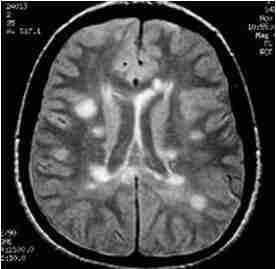

Разными авторами предлагались критерии постановки диагноза. Все они основанный результатах МРТ головного мозга. Главным для постановки диагноза служит наличие нескольких (от 2 до 9) типично расположенных на МРТ очагов. Локализация очагов может быть любая, но типичная - нижняя треть мозолистого тела, перивентрикулярно (вокруг желудочков мозга), ствол, спинной мозг. Форма очагов округлая и овоидная, направленная радиально от желудочков на сагиттальных (боковых) МРТ (симптом “пальца” или Доусона), что отражает перивенулярный (вокруг вен) процесс. Существует много предложений по оценке активности процесса. К сожалению, все способы оценки активности очень недостоверны. Обычно края активных очагов нечёткие, отмечается слабое контрастирование. Чувствительность и специфичность МРТ на самых ранних стадиях составляет 70-80%. Однако через очень короткий срок течения заболевания точность МРТ уже приближается к 100%.

МРТ головного мозга. Рассеянный склероз. Аксиальная МРТ Т2-взвешенного типа. Перивентрикулярные очаги.